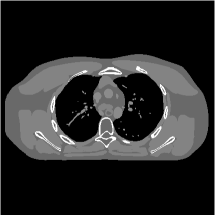

III.C.3. Analysis of Residual Maps

Here, we investigate the residual images over the layers of the MARS7 model. Fig. 12 displays the image reconstructed with MARS7 along with the residual images in different layers. The residual images are generated by applying the restoring operation to the corresponding columns of each residual matrix , forming images . Essentially, all the columns of are transformed into patches and accumulated back in the image to form the residual image in the th layer. We can observe that the residual images in the first three layers contain explicit structural information and we still find some delicate details in the fourth and fifth layers. However, we hardly see any valuable features in the residual images for the following layers, which is consistent with the fact that the transform is overwhelmed by noise in quite deep layers. Therefore, the ceiling for the potential of multi-layer sparsifying transform model may be 5 or 7 layers. The quantitive result also implies the same conclusion.